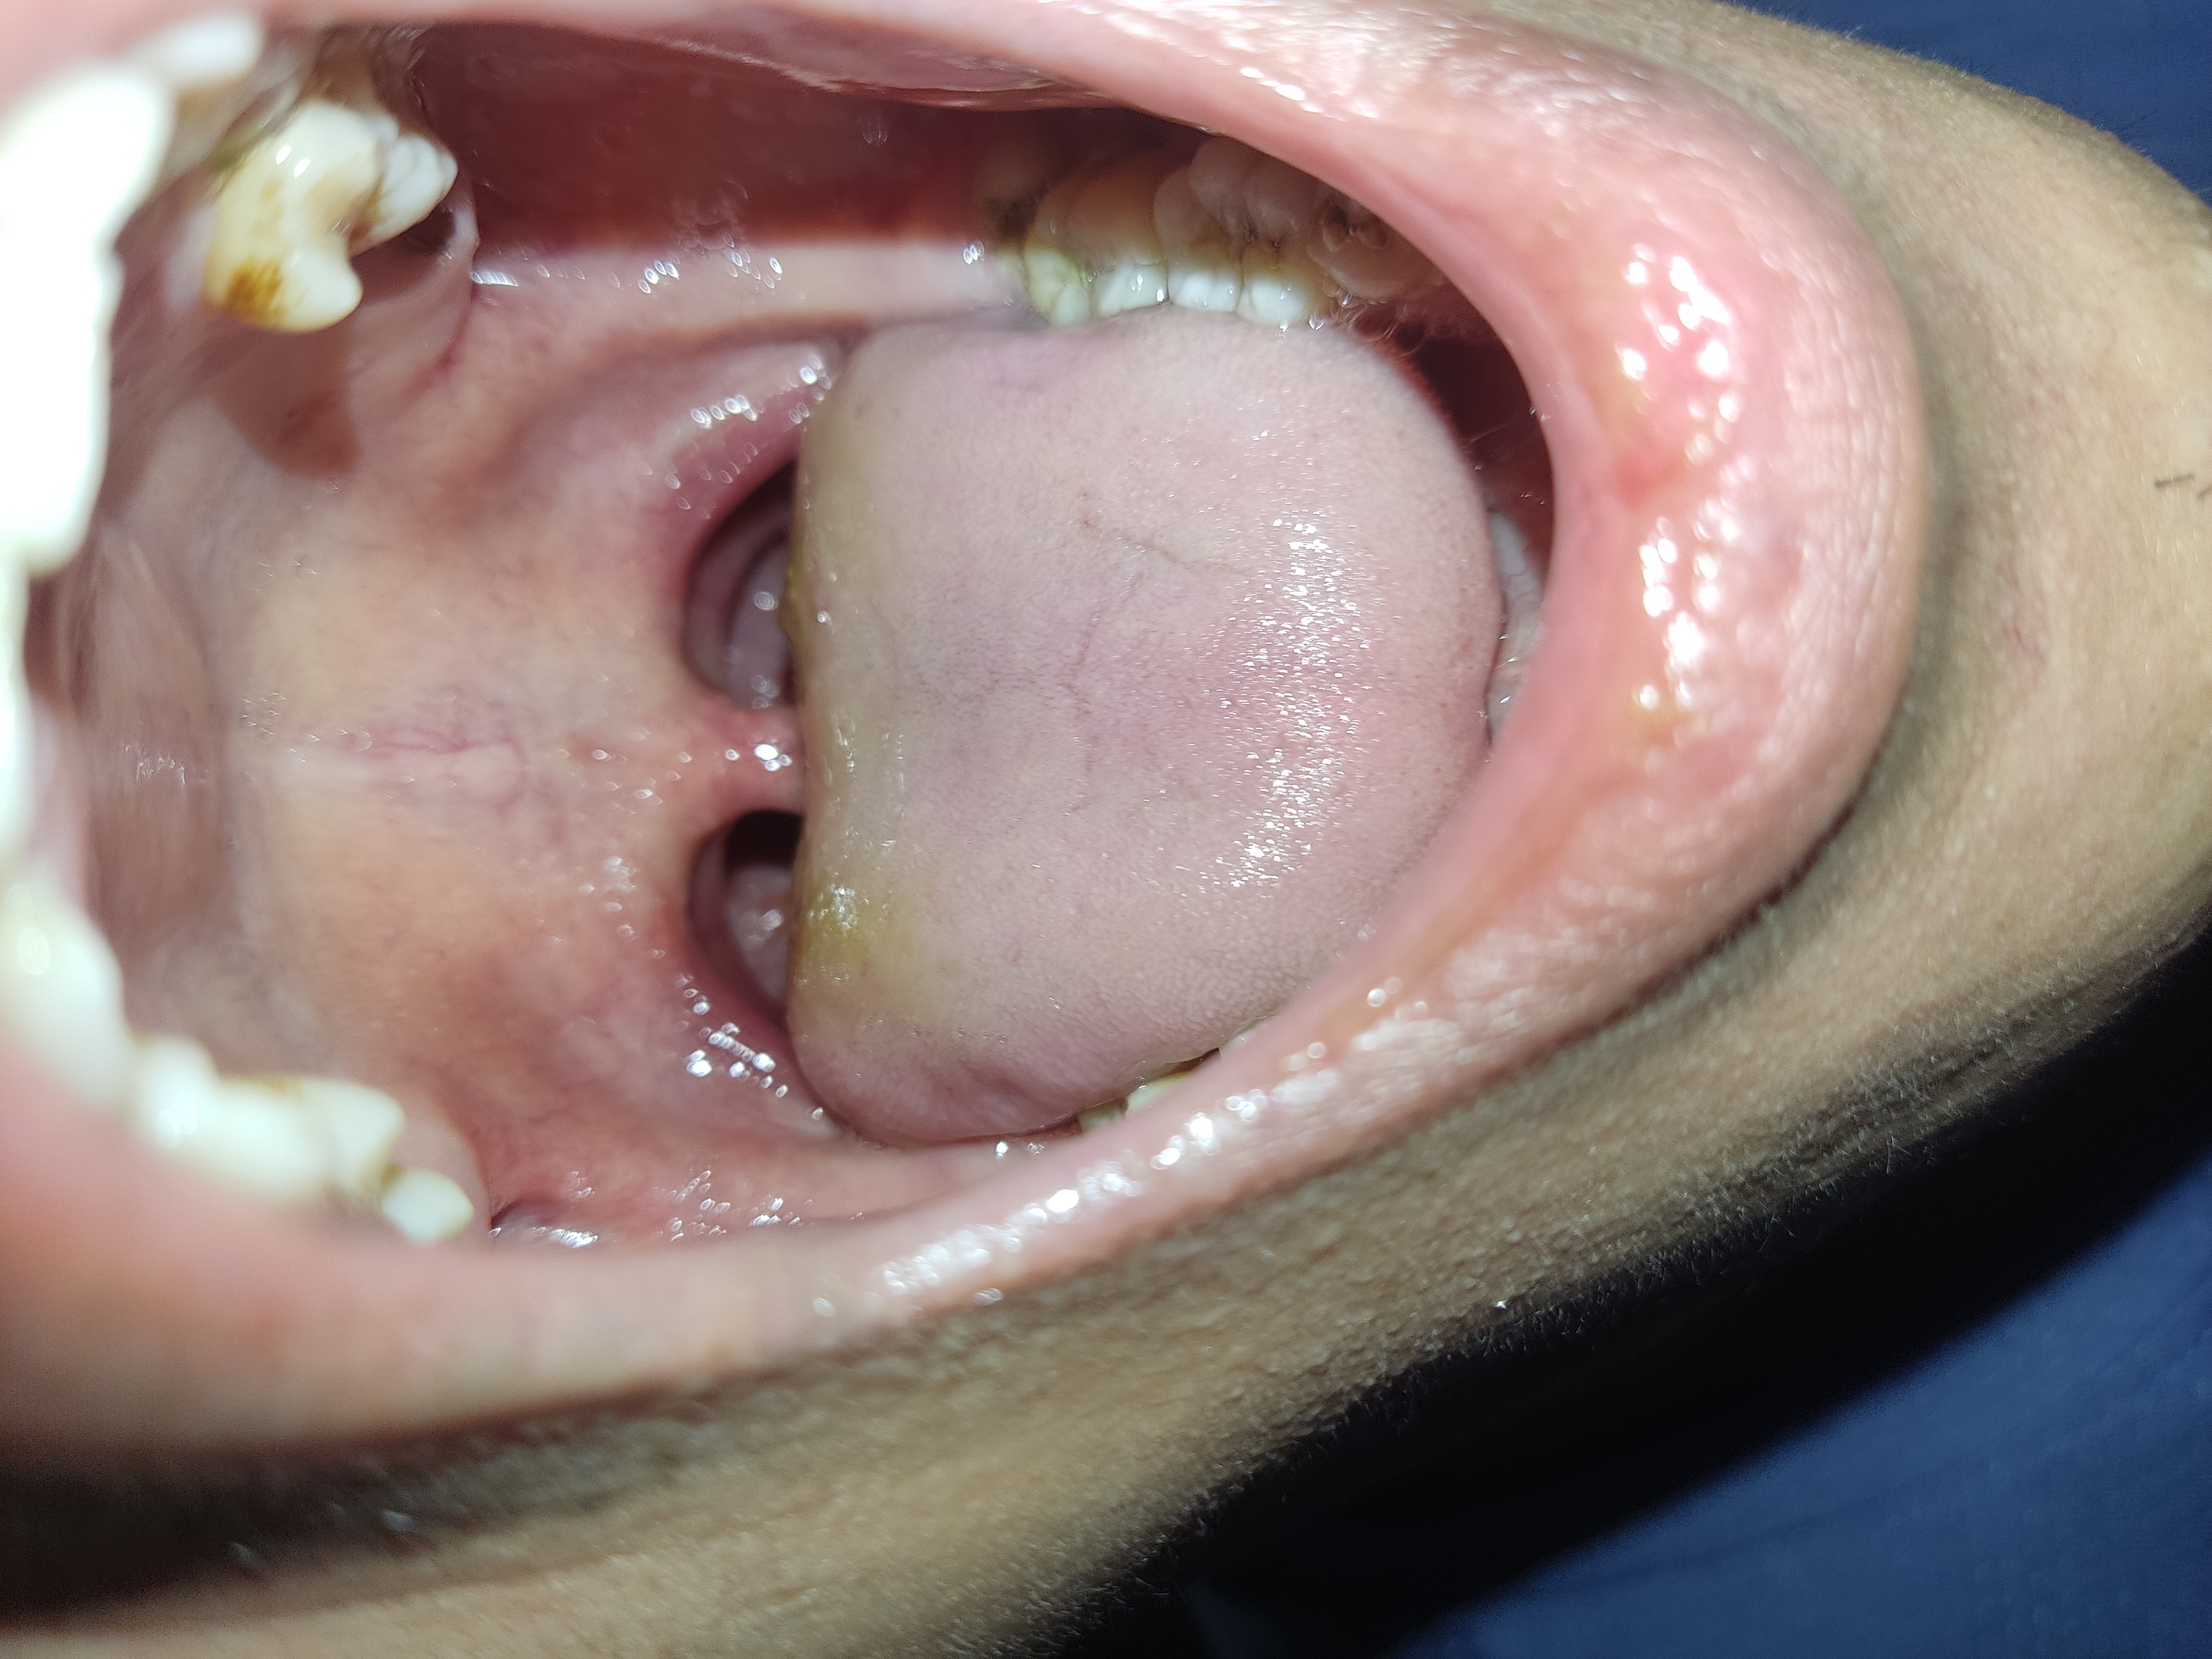

Lưỡi bị trắng

Bắc sĩ Cho em hỏi lưỡi em bị trắng vậy có sao không ạ

Chào em. Lưỡi trắng cần kiểm tra có viêm nhiễm xung quanh như viêm hầu họng hay không. Hoặc viêm nhiễm ở cơ quan khác